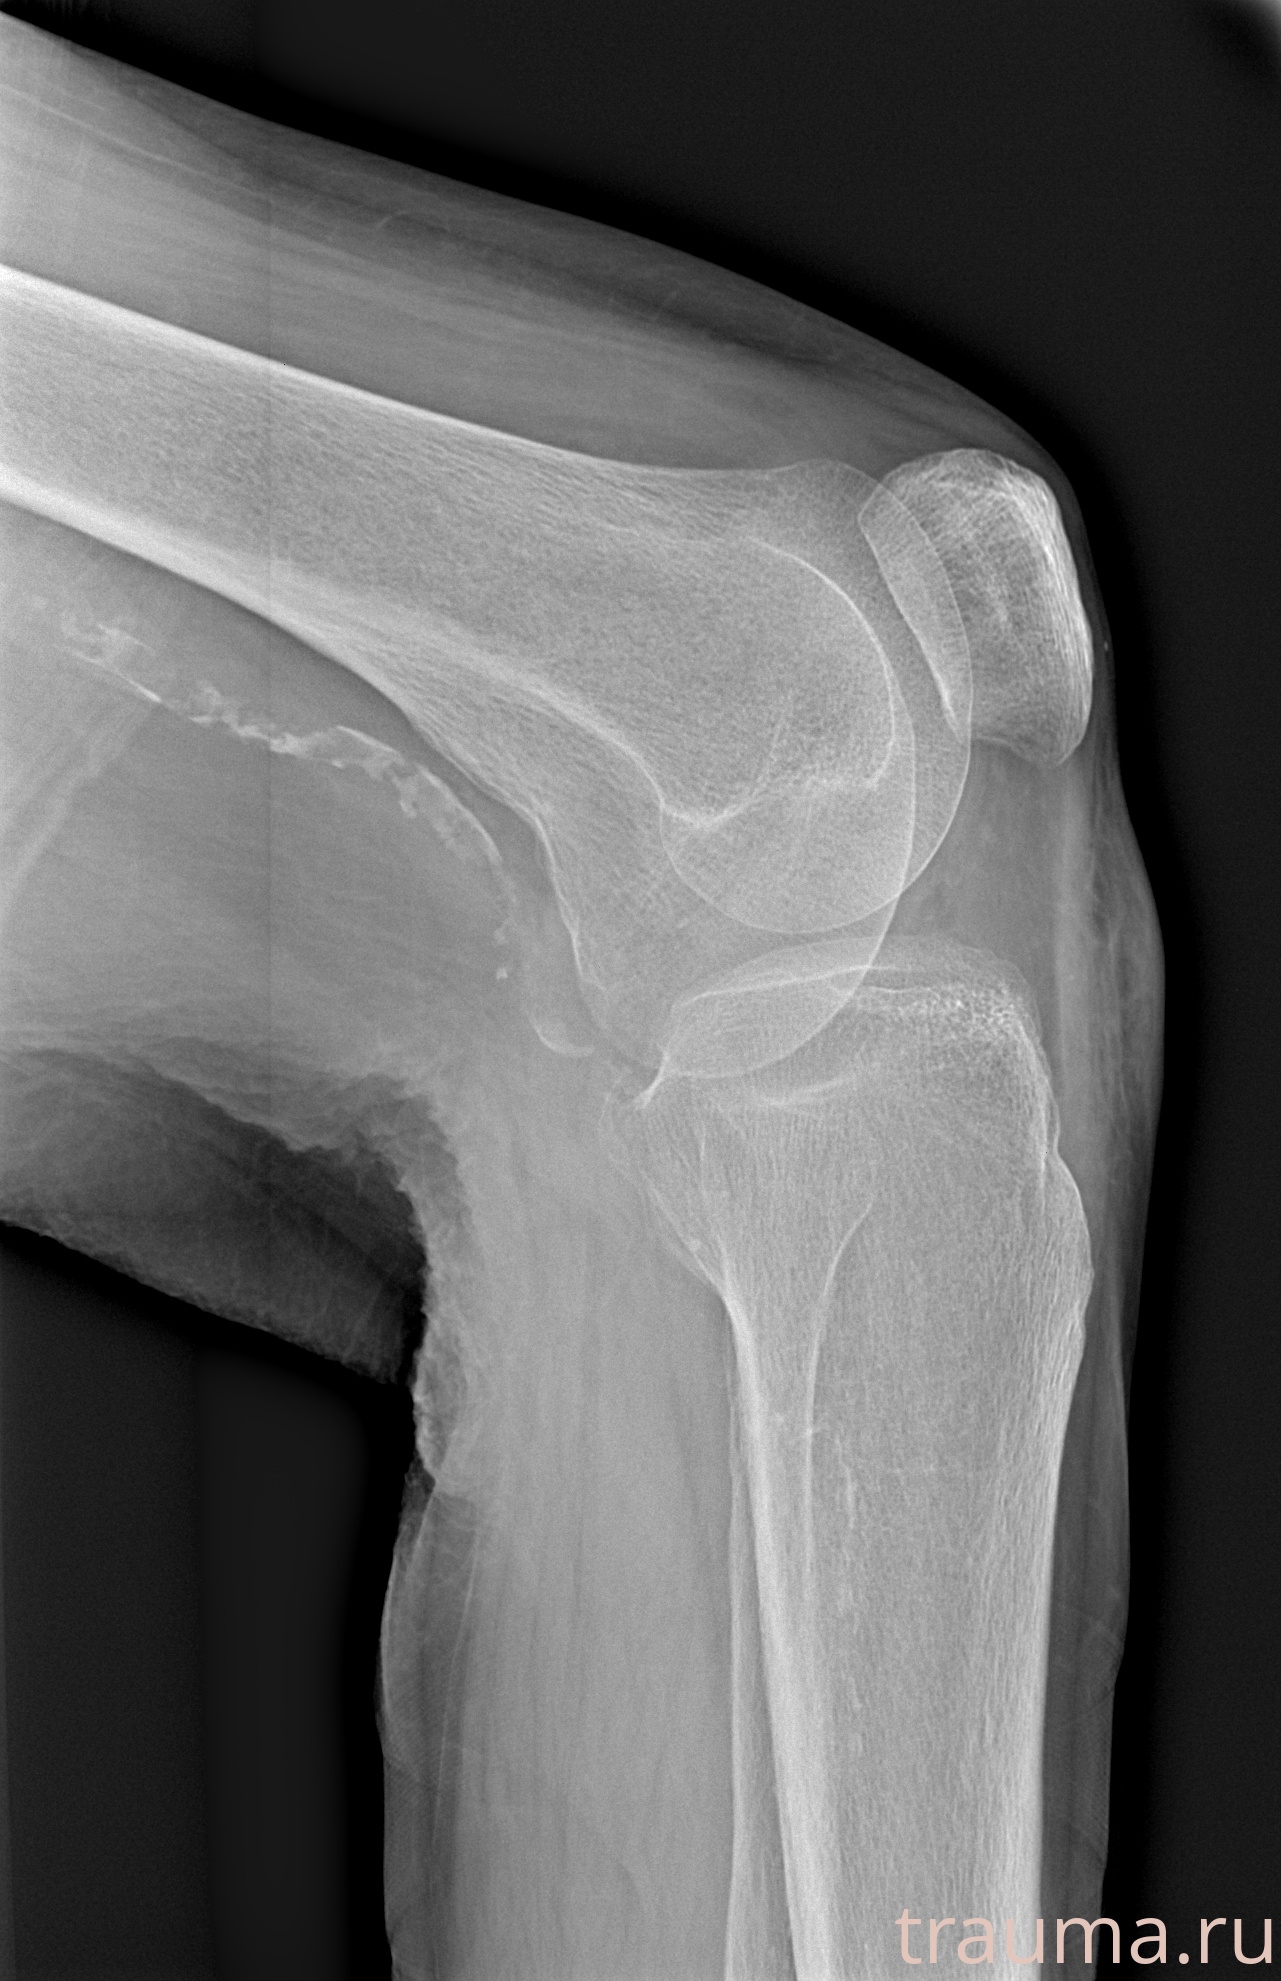

Рентгенограммы

Рентген на дому: по вашему адресу приезжает врач-рентгенолог, травматолог-ортопед с мобильным рентгеновским аппаратом, проводит диагностику травмы или заболевания, делает необходимые рентгенограммы, дает рекомендации по дальнейшему лечению. Получить качественные снимки в домашних условиях возможно благодаря уникальной методике, разработанной МосРентген Центром для института  Склифосовского